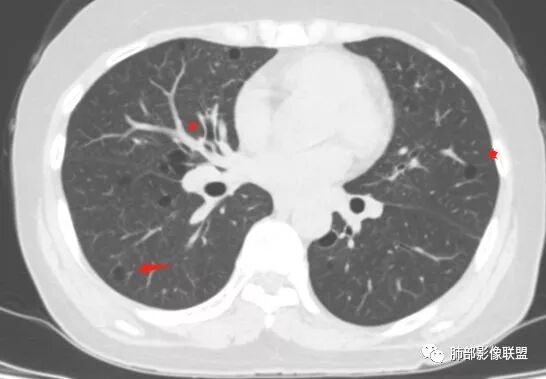

老年女性,眼炎入院,血常规正常,双肺多发囊状影,病变随机分布,形态单一,与血管关系密切,考虑LIP。左下肺混合GGO,边界尚清,贴近囊腔,鉴别腺癌。炎症指标无异常暂不考虑感染性病变。

胸CT:1.双肺多发囊性变,以中下肺为主,病变边缘可见肺动脉,部分囊内可见分隔及肺动脉,双下部分肺野周围可见小叶中心结节及树丫征。

2 左肺上叶尖后段 右肺上叶前段 右肺下叶外基底段 结节影,边界清楚,可见柔软毛刺,左肺下叶后基底段混合密度影。

双肺多发磨玻璃结节,其内可见空腔,周围边界清晰,多发囊,左肺实性结节。考虑间质性肺炎,LIP可能性大。鉴别腺癌。

患者中年女性,因右眼红痛1天就诊。胸CT:双肺多发囊性变及结节影,囊以中下肺为多,部分囊内可见分隔及肺动脉,结节部分为实性,部分为混合性,边缘光滑,未见明显毛刺、棘突、胸膜牵拉及血管集束征象。双中下可见支气管扩张及树丫征。淋巴结无明显肿大。综合考虑:一元淋巴细胞间质性肺炎。多元鉴别肺腺癌并转移等恶性病变。

双肺下叶分布为主的间质改变(磨玻璃影、小叶间隔增厚)、散在气囊影(常有血管贴边)、边界不清小结节